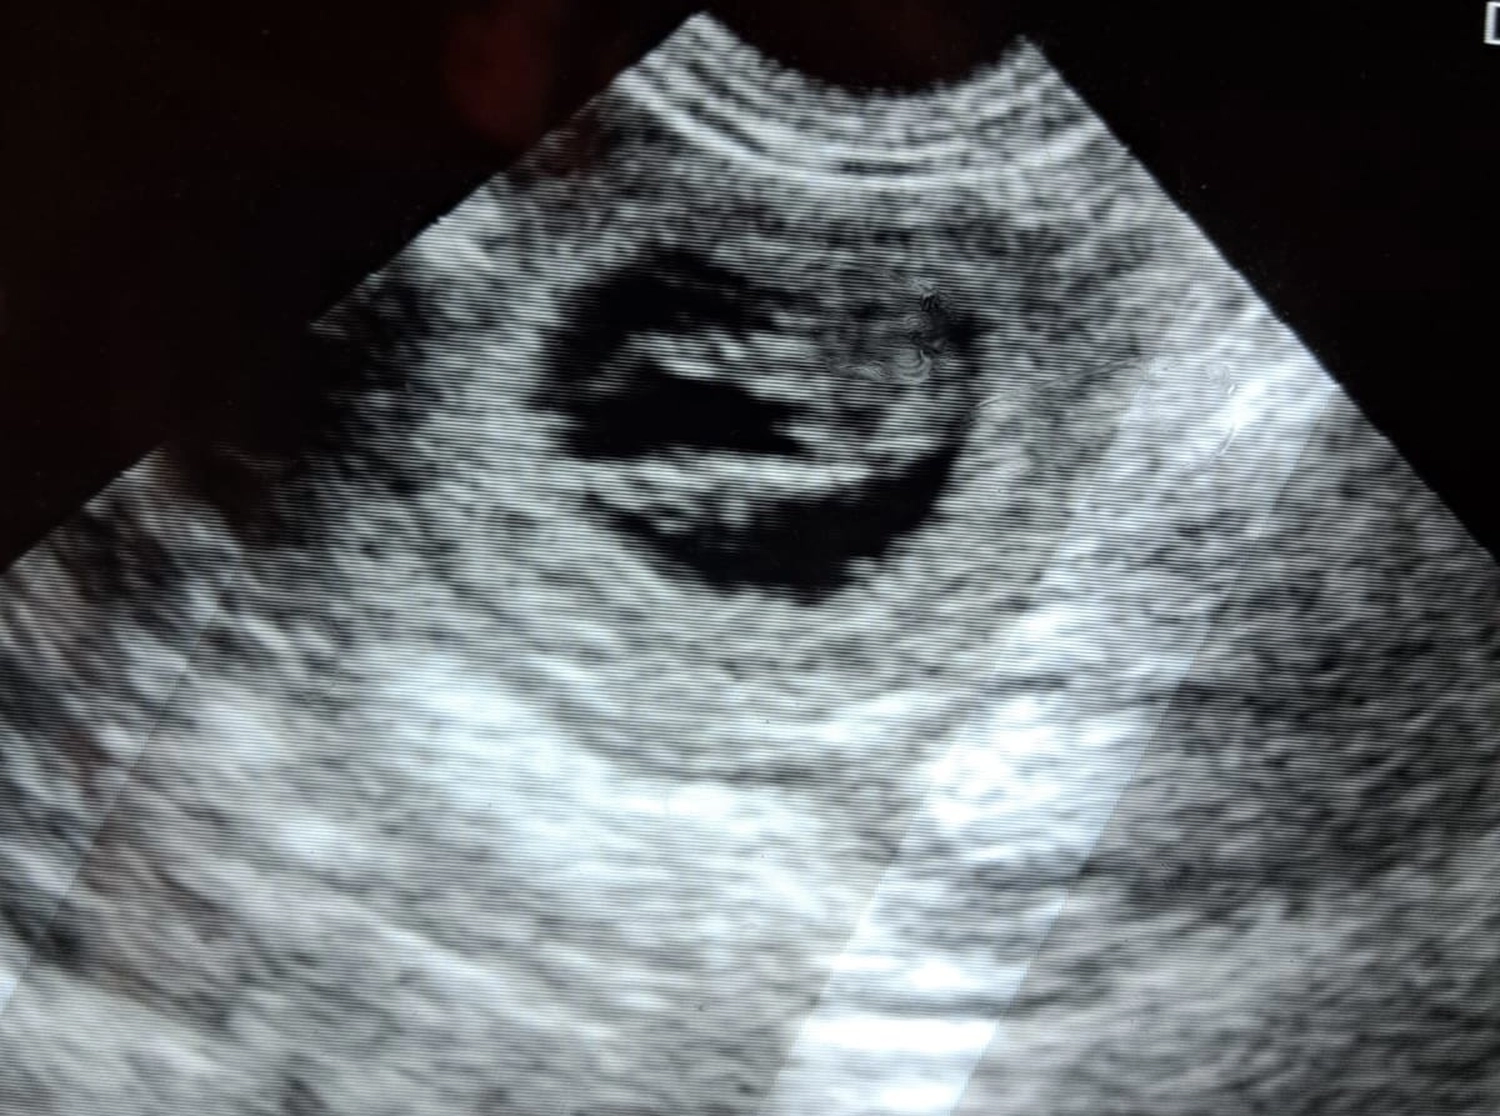

Heute wurde eine Ultraschalluntersuchung von Crazy gemacht, um zu sehen ob sie aufgenommen hat. Lt. Tierarzt ist Crazy tragend, er meinte, "es sind mehrere Welpen drin".

Jetzt heißt es hoffen, dass alles gut geht.